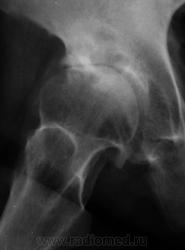

Пол пациента: Мужской пол Тип патологии: Другое Область исследования: Скелетно-мышечная система Методы исследования: Rg Пациент направлен на рентгенографию тазобедренного сустава. https://radiomed.ru/sites/default/files/styles/case_slider_image/public/user/12/2.p2100008.jpg?itok=xeIOIPjU https://radiomed.ru/sites/default/files/styles/case_slider_image/public/user/12/3.p2100008a.jpg?itok=-f8UPzuU ID:12067 Втр, 15/02/2011 - 20:09 #1 Фаина Не на сайте Был на сайте: 2 года 11 месяцев назад Зарегистрирован: 14.12.2008 - 16:51 Публикации: 323 Деф.артроз с кистовидной перестройкой, хотя может эти простветления за счет асептического некроза Втр, 15/02/2011 - 22:49 #2 Петрович Не на сайте Был на сайте: 7 лет 3 месяцев назад Зарегистрирован: 22.03.2009 - 01:13 Публикации: 3908 ДДПКП. Но всё же нужна и прямая проекция Неоднозначно всё Втр, 15/02/2011 - 23:50 #3 Fujimi Не на сайте Был на сайте: 12 лет 6 месяцев назад Зарегистрирован: 20.01.2011 - 23:08 Публикации: 259 Петрович wrote: ДДПКП... Не могли бы Вы расшифровать? Ср, 16/02/2011 - 00:05 #4 Петрович Не на сайте Был на сайте: 7 лет 3 месяцев назад Зарегистрирован: 22.03.2009 - 01:13 Публикации: 3908 ДДПКП = Дегенеративно-дистрофическое поражение с кистовидной перестройкой. Одно из трёх дегенеративно-дистрофических поражений, выделяемых/описанных Н.С. Косинской. Могу дать почитать её Классический труд. Неоднозначно всё Ср, 16/02/2011 - 00:12 #5 Fujimi Не на сайте Был на сайте: 12 лет 6 месяцев назад Зарегистрирован: 20.01.2011 - 23:08 Публикации: 259 Спасибо. У меня есть. Так можно писать в заключении? Ср, 16/02/2011 - 00:14 #6 Петрович Не на сайте Был на сайте: 7 лет 3 месяцев назад Зарегистрирован: 22.03.2009 - 01:13 Публикации: 3908 Я пишу. С указанием стадии. Неоднозначно всё Ср, 16/02/2011 - 00:17 #7 Fujimi Не на сайте Был на сайте: 12 лет 6 месяцев назад Зарегистрирован: 20.01.2011 - 23:08 Публикации: 259 Большое Вам спасибо! Пт, 18/02/2011 - 22:00 #8 Катенёв Валенти... Не на сайте Был на сайте: 7 лет 1 месяц назад Зарегистрирован: 22.03.2008 - 22:15 Публикации: 54876 Спасибо за высказанные мнения. Сб, 19/02/2011 - 10:12 #9 Евгений1313 Не на сайте Был на сайте: 13 лет 2 недели назад Зарегистрирован: 15.10.2010 - 19:13 Публикации: 808 Так то оно так ,да только кистозная перестройка чаше поражает головку, а здесь она интактная.И напротив-ограниченный участок деструкции в области "крыши" вертлужной впадины.Я думаю что это метастаз в ости впадины. Сб, 19/02/2011 - 18:39 #10 Петрович Не на сайте Был на сайте: 7 лет 3 месяцев назад Зарегистрирован: 22.03.2009 - 01:13 Публикации: 3908 Для суждения об интактности головки всё же необходима прямая проекция. Метастаз если есть, то не один. И миеломная не исключается вовсе. Неоднозначно всё

Деф.артроз с кистовидной перестройкой, хотя может эти простветления за счет асептического некроза

ДДПКП. Но всё же нужна и прямая проекция

Так то оно так ,да только кистозная перестройка чаше поражает головку, а здесь она интактная.И напротив-ограниченный участок деструкции в области "крыши" вертлужной впадины.Я думаю что это метастаз в ости впадины.

Для суждения об интактности головки всё же необходима прямая проекция. Метастаз если есть, то не один. И миеломная не исключается вовсе.